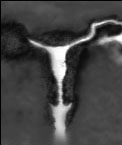

HSG

Хистеросалпингографията (HSG) е рентегнова снимка използвана за установяване на запушвания на тръбите и маточни проблеми. Инжектира се контрастно вещество през шийката на матката и се прави рентгеновата снимка. Това изследване се прави обикновено след менструация и преди овулация.

инжектирано контрастно вещество